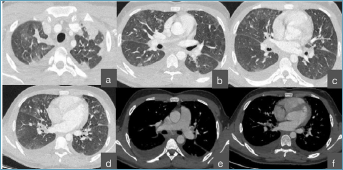

CT scan lung window demonstrated smooth interlobular septal thickening predominantly in the upper lobes, with associated focal patchy consolidations and mild ground-glass opacities in the middle lobe and lingual (Fig. 1). Moderate bilateral pleural effusions was also visible. On the mediastinal window, no pulmonary embolism or left atrial enlargement were detected.

Figure 1.(a-d) Interlobular septal thickening - lung window. (e-f) No evidence of pulmonary embolism or left atrial enlargement -mediastinal window.